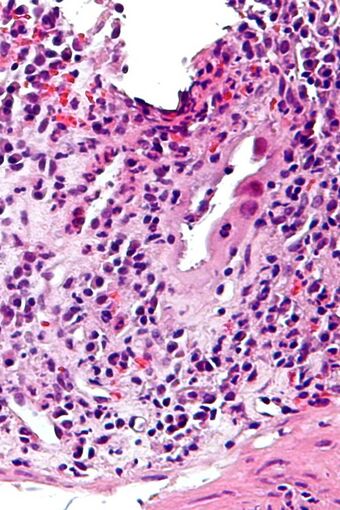

| Micrograph of CMV colitis. H&E stain. |

Because asymptomatic CMV viremia and viruria is common and about 1/3 of symptomatic CMV infection is caused by reinfection of different strain of CMV, the diagnosis of CMV colitis needs more direct causality. It is practically achieved by colonoscopy or sigmoidoscopy tissue sampling and pathological evidence of CMV infection under microscope, more specifically macroscopic picture will show many ulcers that appear on the mucous membrane and microscopically the biopsy will show intranuclear and cytoplasmic inclusion bodies. Positive CMV IgG doesn't necessarily mean that it is reactivation of latent infection because of the possibility of reinfection of different strain.[citation needed]